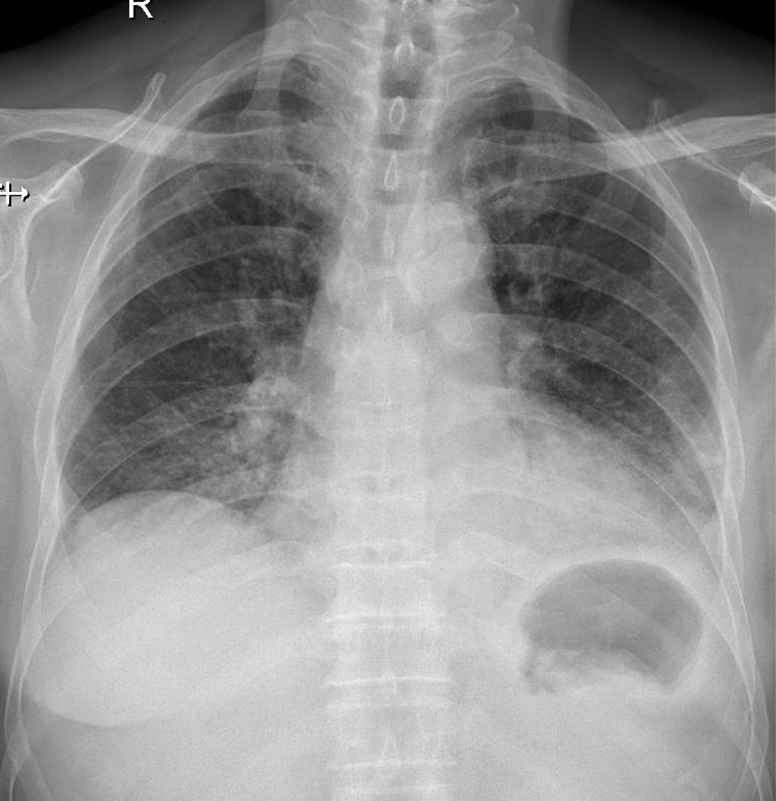

1-Thâm nhiễm phế nang lan tỏa thùy dưới hai phổi => Viêm phổi 2-Bóng tim to 3-Gãy cũ cung sườn sau (P): 3, 4